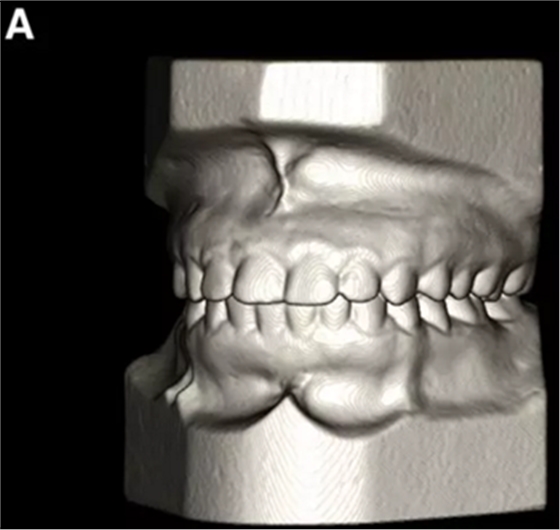

患者的上頜骨和下頜骨研究模型在最大牙尖交錯(cuò)位時(shí)確定和數(shù)字化(圖2,A),作為咬合指導(dǎo)(咬合指導(dǎo))。該數(shù)字化咬合指導(dǎo)在齦緣周圍進(jìn)行數(shù)字化修剪,以便在CBCT掃描上可以更好得可視化(圖2,B)。

圖2. A,咬合時(shí)對象研究模型的右側(cè)舌側(cè)視圖掃描將作為未來指導(dǎo);該指導(dǎo)稍后用于將懸浮的下頜骨配對到修剪的上頜骨;B,左側(cè)舌側(cè)視圖的數(shù)字化修整牙合引導(dǎo)。